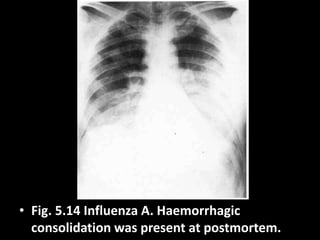

• Fig. 5.14 Influenza A. Haemorrhagic

consolidation was present at postmortem.

• Fig. 5.14Influenza A. Haemorrhagic consolidation was present at postmortem.